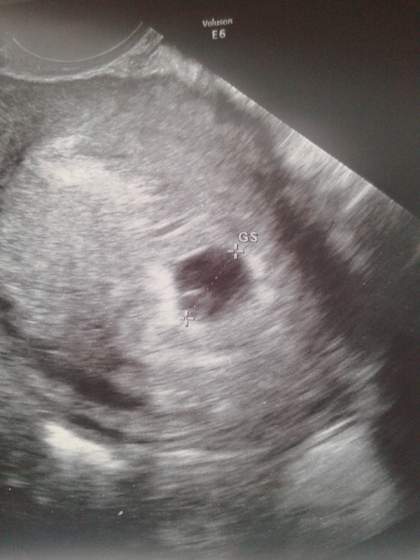

Wrzucę wam zdjęcie jakie dostałam ostatnio pęcherzyk z zarodkiem 20141209_135336.jpg

Dziolszki a moze zalozymy osobny temat, w ktorym bedziemy wrzucac zdjecia z usg? :) Beata, takie malenstwo, ze wcale sie nie dziwie ze serduszka nie bylo widac :) W nastepnym tyg juz bedzie pieknie bilo :-)

Mama jiz zadroszcze sniegu... A co do pustego pecherzyka to chyba wszystkie mamy takie obawy. Ale trzeba myslec pozytwnie i napewno na najblizszej wizycie bdzie juz bilo serduszko

Beata ale malenstwo. Piekne. A za tydzien bedzie wieksze i z bijacym serduszkiem :-)